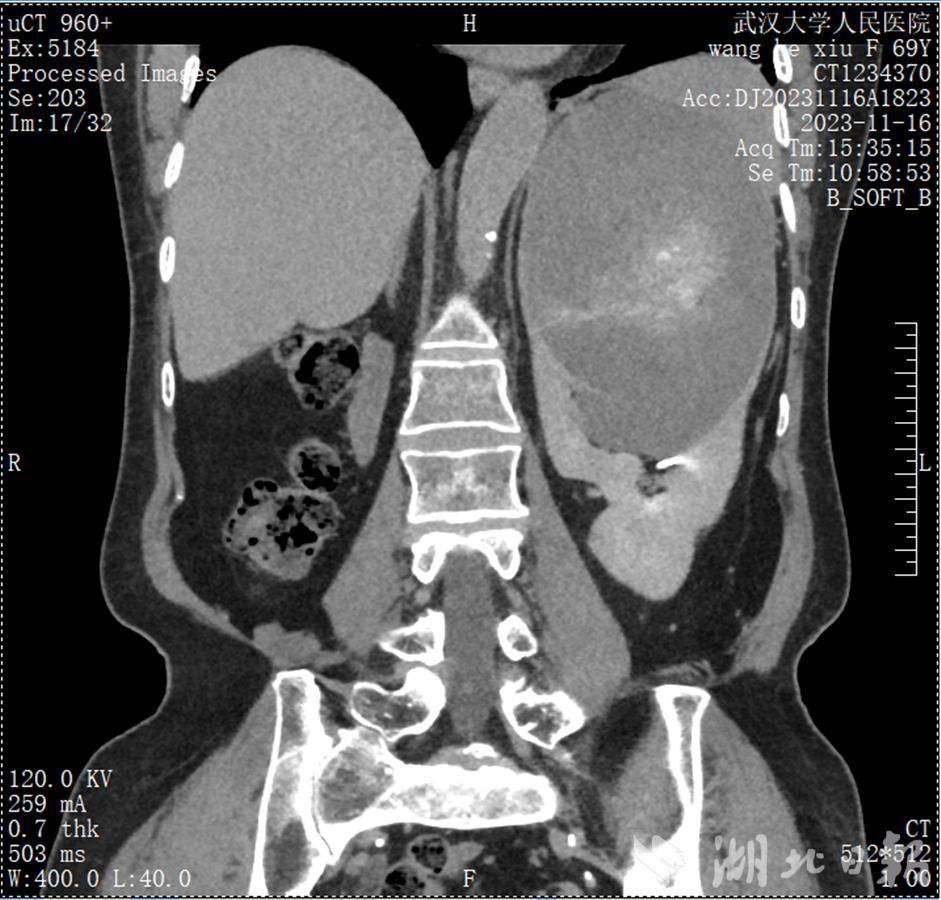

因腰疼上医院检查,王奶奶意外发现自己先天性只有左肾,更想不到的是,左肾藏有一颗近15厘米的巨大肿瘤。近日,武汉大学人民医院东院泌尿外科团队妙手极限“拆弹”保肾,为王奶奶切除了肿瘤,保全这颗宝贵的独肾,避免患者余生依赖透析生存。

“肿瘤位于左肾上极和中部,超过肾门动静脉。如果行肾部分切除术,既要完整彻底切除肿瘤,否则肿瘤容易复发;同时又不能损伤动静脉,而且需要尽可能多地保留肾实质,手术难度极大。”祝恒成直言不讳地说,即便手术,术后因肾脏太小,患者仍有透析可能性,常规需行根治性肾切除。

祝恒成介绍,肾癌在疾病早期阶段一般没有明显症状。如果出现腰痛、血尿和腹部肿块,往往提示病程相对较晚。如果肿瘤大于10cm,保肾手术的难度会明显增加,而且术后复发的可能性也会增加。他提醒,有肾癌家族史的人,应该每年定期检查B超或CT,以期做到“早发现、早诊断、早治疗”。